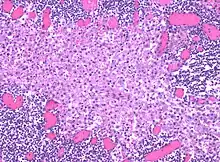

Histiocytosis is a group of disorders that result in excessive number of histiocytes (dendritic cells or monocyte macrophages).[1] Symptoms are variable.[2] Commonly affected organs include skin, bone, lungs, lymph nodes, nervous system, and heart.[2]

The underlying mechanism may involved genetic changes in the mitogen-activated protein (MAP) kinase cell-signaling pathway.[2] Diagnosis is based on tissue biopsy, symptoms, and medical imaging.[2] Types include Langerhans cell histiocytosis (LCH), juvenile xanthogranuloma, Erdheim-Chester disease, hemophagocytic syndrome, and Rosai-Dorfman disease.[1]